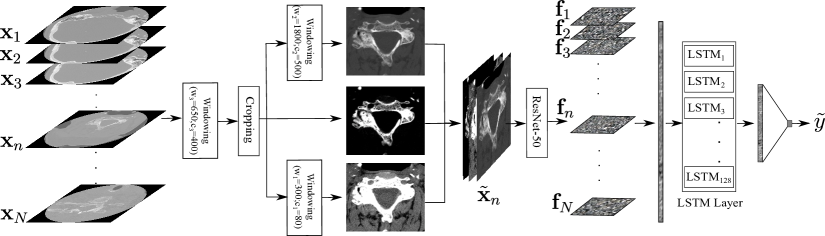

Refer to caption

Fig. 1: Proposed model for fracture detection on cervical spine scans. The input scan has N𝑁N axial images and the BLSTM layer has 128 LSTM units.

2 Fracture Detection in Cervical Spine

A cervical spine CT has N𝑁N number of axial image slices along the cranio-caudal axis where we represent each image with a vector 𝐱nsubscript𝐱𝑛\mathbf{x}_{n}. Therefore, we can model the cervical spine as the set of input images 𝐗=(𝐱1,𝐱2,,𝐱N)𝐗subscript𝐱1subscript𝐱2subscript𝐱𝑁\mathbf{X}=(\mathbf{x}_{1},\mathbf{x}_{2},...,\mathbf{x}_{N}) with the corresponding image level labels 𝐲=(y1,y2,,yN)𝐲subscript𝑦1subscript𝑦2subscript𝑦𝑁\mathbf{y}=(y_{1},y_{2},...,y_{N}), where yn=1subscript𝑦𝑛1y_{n}=1 means the image contains at least one fracture and yn=0subscript𝑦𝑛0y_{n}=0 is the opposite. We can also define a case level label y{0,1}𝑦01y\in\{0,1\}, where if y=1𝑦1y=1 at least one image contains a fracture and if y=0𝑦0y=0 none of the images contain a fracture. Figure 1 shows different steps of the proposed model. It has two major steps, which are prepossessing of the input images 𝐗𝐗\mathbf{X} and learning a mapping function from the preprocessed images to the target y𝑦y. Different steps are discussed as follows.

For the image 𝐱n𝐗subscript𝐱𝑛𝐗\mathbf{x}_{n}\in\mathbf{X}, the preprocessed images are concatenated as 𝐱~n=(𝐱~n(1)𝐱~n(2)𝐱~n(3))subscript~𝐱𝑛direct-sumsuperscriptsubscript~𝐱𝑛1superscriptsubscript~𝐱𝑛2superscriptsubscript~𝐱𝑛3{\tilde{\mathbf{x}}_{n}=(\tilde{\mathbf{x}}_{n}^{(1)}\oplus\tilde{\mathbf{x}}_{n}^{(2)}\oplus\tilde{\mathbf{x}}_{n}^{(3)})} where direct-sum\oplus is the concatenation operator. The cervical spine images have spatiotemporal dependency. First, ResNet-50 [9] is trained using randomly selected batches of images from all training cases. The objective is to train ResNet-50 as the function 𝐅=ϕ(𝐗~)𝐅italic-ϕ~𝐗\mathbf{F}=\phi(\tilde{\mathbf{X}}) where 𝐟n𝐅subscript𝐟𝑛𝐅\mathbf{f}_{n}\in\mathbf{F} is the extracted feature map from 𝐗~n𝐗subscript~𝐗𝑛𝐗\tilde{\mathbf{X}}_{n}\in\mathbf{X}. As Figure 1 shows, the feature maps are vectorized and concatenated as 𝐟~=(𝐟1𝐟2,,𝐟N)~𝐟direct-sumsubscript𝐟1limit-fromsubscript𝐟2direct-sumsubscript𝐟𝑁\tilde{\mathbf{f}}=(\mathbf{f}_{1}\oplus\mathbf{f}_{2}\oplus,...,\mathbf{f}_{N}). The second phase is learning the temporal dependency among axial images using a bidirectional network of LSTM units to map 𝐟~~𝐟\tilde{\mathbf{f}} to the case label y𝑦y. The loss is calculated using binary cross-entropy function with respect to the target label y𝑦y. In the inference mode, the feature extractor ϕ()italic-ϕ\phi(\cdot) and BLSTM layer work together for a given case 𝐗𝐗\mathbf{X} to generate the inference y~~𝑦\tilde{y}.